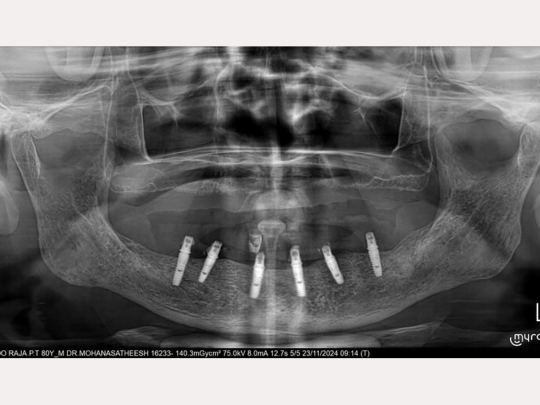

Implant

Before and After